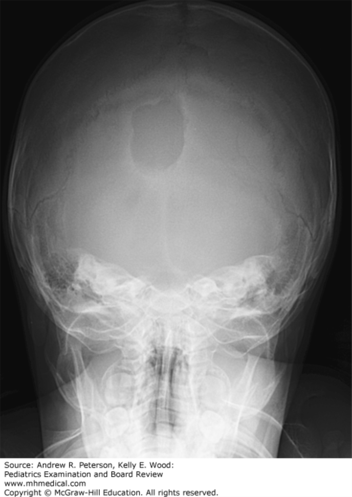

Her parents first noticed them several weeks ago and thought they were “zits” because they were soft and painless. Now, the lumps have grown and are still soft and painless. The patient has previously been healthy, although the parents report that she has been getting up five to eight times each night to void, and is drinking more than usual for the past 2 to 3 weeks. Vital signs are within normal limits. Physical exam is remarkable for soft, nontender nodules over the right temporal bone and right occipital scalp. You also notice a rash on the right pinna, which is scaly and erythematous, and which the patient reports has been there for months; it is occasionally pruritic. A skeletal X-ray series is performed, and reveals a 1.5 × 1.5 cm round, lytic lesion in the right temporal bone and another 2.5 × 3 cm similar lesion in the right occipital bone, the latter of which is shown in Figure 4–5.

FIGURE 4–5.

Skull finding in Langerhans cell histiocytosis (LCH). This plain film exhibits a large lytic lesion in the right occipital bone. There is minimal sclerosis and no periosteal reaction. This appearance is consistent with skull lesions common in LCH. (Used with permission from Adam D. Wolfe, MD, PhD.)